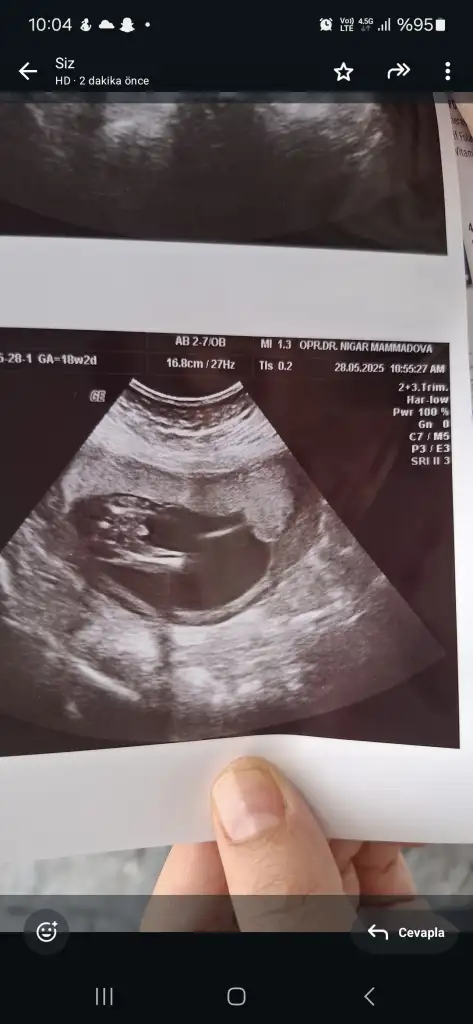

Bana da yapay zeka ve erkek gibi dedi doktor da %95 erkek dedi bakalım bende sanmıyorum bu haftadan sonra dönmez ama yine de detaylı ulturasyon dan sonra kıyafet alırım diyorumİlk görüntüde (18 hafta 2 günlük olduğu yazıyor), genital bölge biraz daha belirgin olabilir. Görüntüde bacaklar arasında çıkıntı gibi görünen bir yapı var gibi, bu da erkek bebek olabileceğini düşündürebilir.

Doktor 17 haftaya girerken iki kez yüzde 80 kız dedi daha sonra 18+2 de gittim %99 erkek dedi bu şekilde olan değişen varmı 22 haftada detaylı ultrason giricem iyice muallakta kaldım

Bende ilk fotoda 3 çizgi gibi gördüm sonraki foto da pipi bilmiyorum artık en son Doktor 99 erkek dedi ulturasyon da netleşir sanırımilk fotoda kız gördüm 3 çizgi gibi 3. fotodada pipi gördüm :)